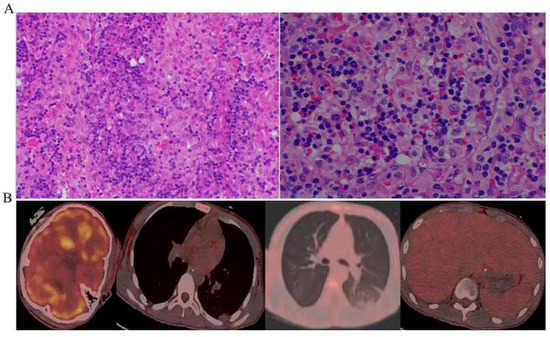

| Hemophagocytosis in bone marrow lymph nodes, spleen, or liver | Yes |